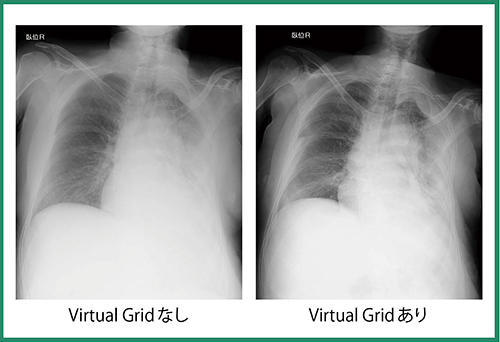

CALNEO Go,CALNEO flexおよびFPDを導入したことで,撮影におけるワークフローが向上し,検査時間の大幅な短縮,カセッテ運搬・交換の負担軽減および患者の身体的負担の軽減,医師による素早い画像確認など,多くのメリットが得られた。また,

Virtual Gridを用いることで低被ばくでも高画質が得られており(図2),診療の質の向上にもつながっている。今後は,Virtual Gridの適用範囲のさらなる拡大にも期待したい。

図2 Virtual Gridの有無による画像比較